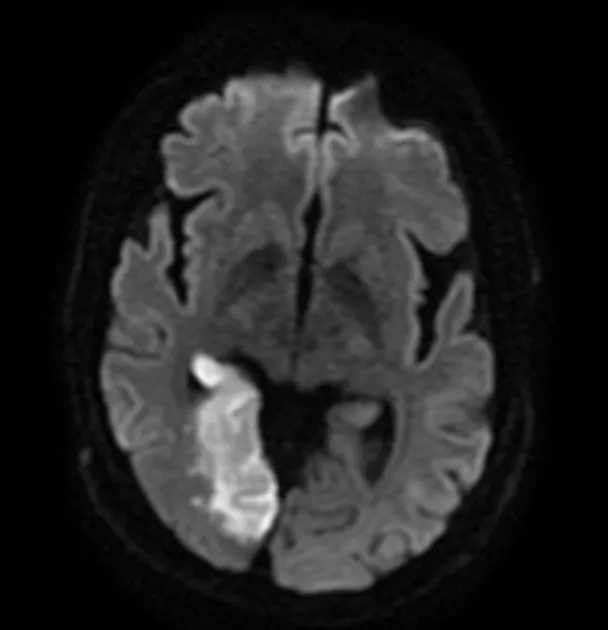

Ischaemic stroke pathophysiology centres on the ischaemic penumbra-tissue surrounding the infarct core that remains viable for 4.5-6 hours through collateral circulation. This penumbra represents salvageable brain: each minute of untreated large vessel occlusion destroys 1.9 million neurons. Thrombolysis and thrombectomy target penumbral rescue, explaining strict time windows. Haemorrhagic transformation risk increases with larger infarcts, delayed reperfusion, and anticoagulation, occurring in 15% of ischaemic strokes.

Stroke imaging :

| MRI brain with DWI | First seizure, diagnostic uncertainty | Structural lesion 10-15% |